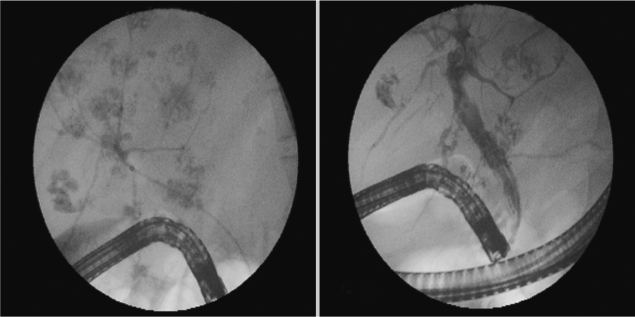

In January 2010, a 37-year-old woman complained of icterus, ascites, and pain in her right upper abdominal region. She was living in a village of southeast of Anatolia region, and she had sheeps and cows. She had the eating history of lettuce, mallow, dill, and parsley without washing. She had no history of using hepatotoxic drugs. On admission to our department, her temperature was 37.9℃, and she had icterus, hepatomegaly, and ascites. Over the 3-month period, her weight dropped from 70 kg to 58 kg. Laboratory findings revealed an increase in leukocytes, aspartate aminotransferase (AST), alanine aminotransferase (ALT), and bilirubin levels. CT scans revealed reticular patterns at all segments of the liver parenchyme, and in affinity with each other about 6 cm in greatest diameter, lobulated contours in multiple views with some cystic lesions were de-tected. After contrast agent injection, mild peripheral enhancement of the lesions were seen in the majority (abscess-phleg-mon was considered). She had yellow color ascites and splenomegaly. ERCP was addressed at F. gigantica because of their different appearance. Her eosinophilia was about 26.4%. The IgE level was 1,170 IU/ml (normal: 0-350 IU/ml). The serum collected when the fluke emerged yielded a titer of 1:20,480 by a standard ELISA protocol (reference: <1,160). In the ascites, serum ascites albumine gradient (SAAG) was under 1.1. We applied ERCP procedure to the patient. We removed 7 live F. gigantica worms during the ERCP (Fig. 1). On the basis of its morphology and shape, the fluke was diagnosed as F. gigantica, and a portion was kept in 70% ethanol (Fig. 2). The eggs of F. gigantica are seen in Fig. 3. A single dose of triclabendazole (3 tablets, oral) was administered. After these therapy, clinical symptoms disappeared and the patient remained completely healthy.

Parasite removal during ERCP is a therapeutic option in patients with acute obstructive cholangitis due to F. gigantica [11]. Triclabendazole at a single dose of 10 mg/kg is the chemotherapeutic regimen of choice against fascioliasis [12]. The drug is active against both immature and adult parasites, with high cure rates. Our case had chronic and hepatobiliary phase of fascioliasis. ERCP findings of parasites was very interesting (such as foodprints of parasites) (Fig. 1). We think this is a highly specific appearance for fascioliasis. The present F. gigantica patient is the first case which was treated via endoscopic biliary extraction during ERCP and drug in Turkey.